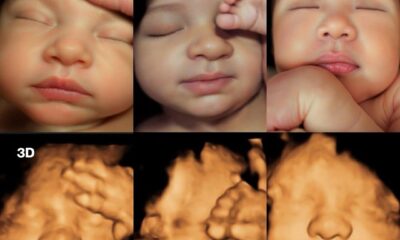

Sensasi Baru! USG 4D Ditingkatkan Pakai Ai dan 8K Jadi Potret Bayi Super Detil

Dalam beberapa tahun terakhir, perkembangan teknologi ultrasound untuk kehamilan mengalami revolusi signifikan. Dari gambar USG 2D yang buram dan datar, kini para orang tua dapat menikmati...